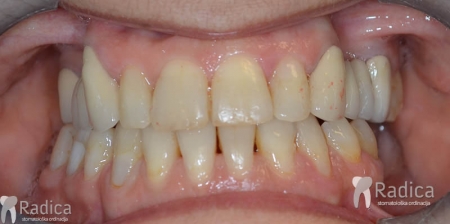

U ovom slučaju je 41.godinu starom pacijentu počeo nicati impaktirani desni gornji očnjak pri čemu je ugrozio lateralni sjekutić. Pacijentu je stavljen fiksni aparat te je zub smješten u luk. Kako je pacijent odustao od postave aparata u donjoj čeljusti na kraju nije dobivena zadovoljavajuća okluzija na što je upozoren.